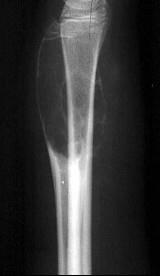

问题 男性,17岁,近2年来感右前臂疼痛,肿胀,2周前由于疼痛加剧,查体右前臂压痛明显,皮肤稍显红肿,请结合所提供图像,选择最佳选项()

选项 A.骨囊肿 B.巨骨细胞瘤 C.动脉瘤样骨囊肿 D.软骨瘤 E.骨血管球瘤

答案 C